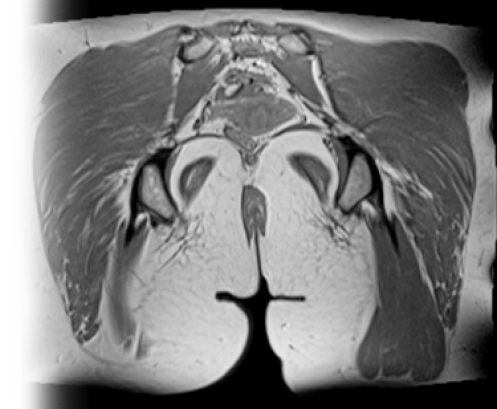

МРТ мягких тканей ягодичной зоны с контрастом

Магнитно-резонансная томография мягких тканей ягодичной зоны с контрастированием – важный метод исследования с введением контраста, который позволяет визуализировать мышцы, связки, сухожилия, подкожно-жировую клетчатку.